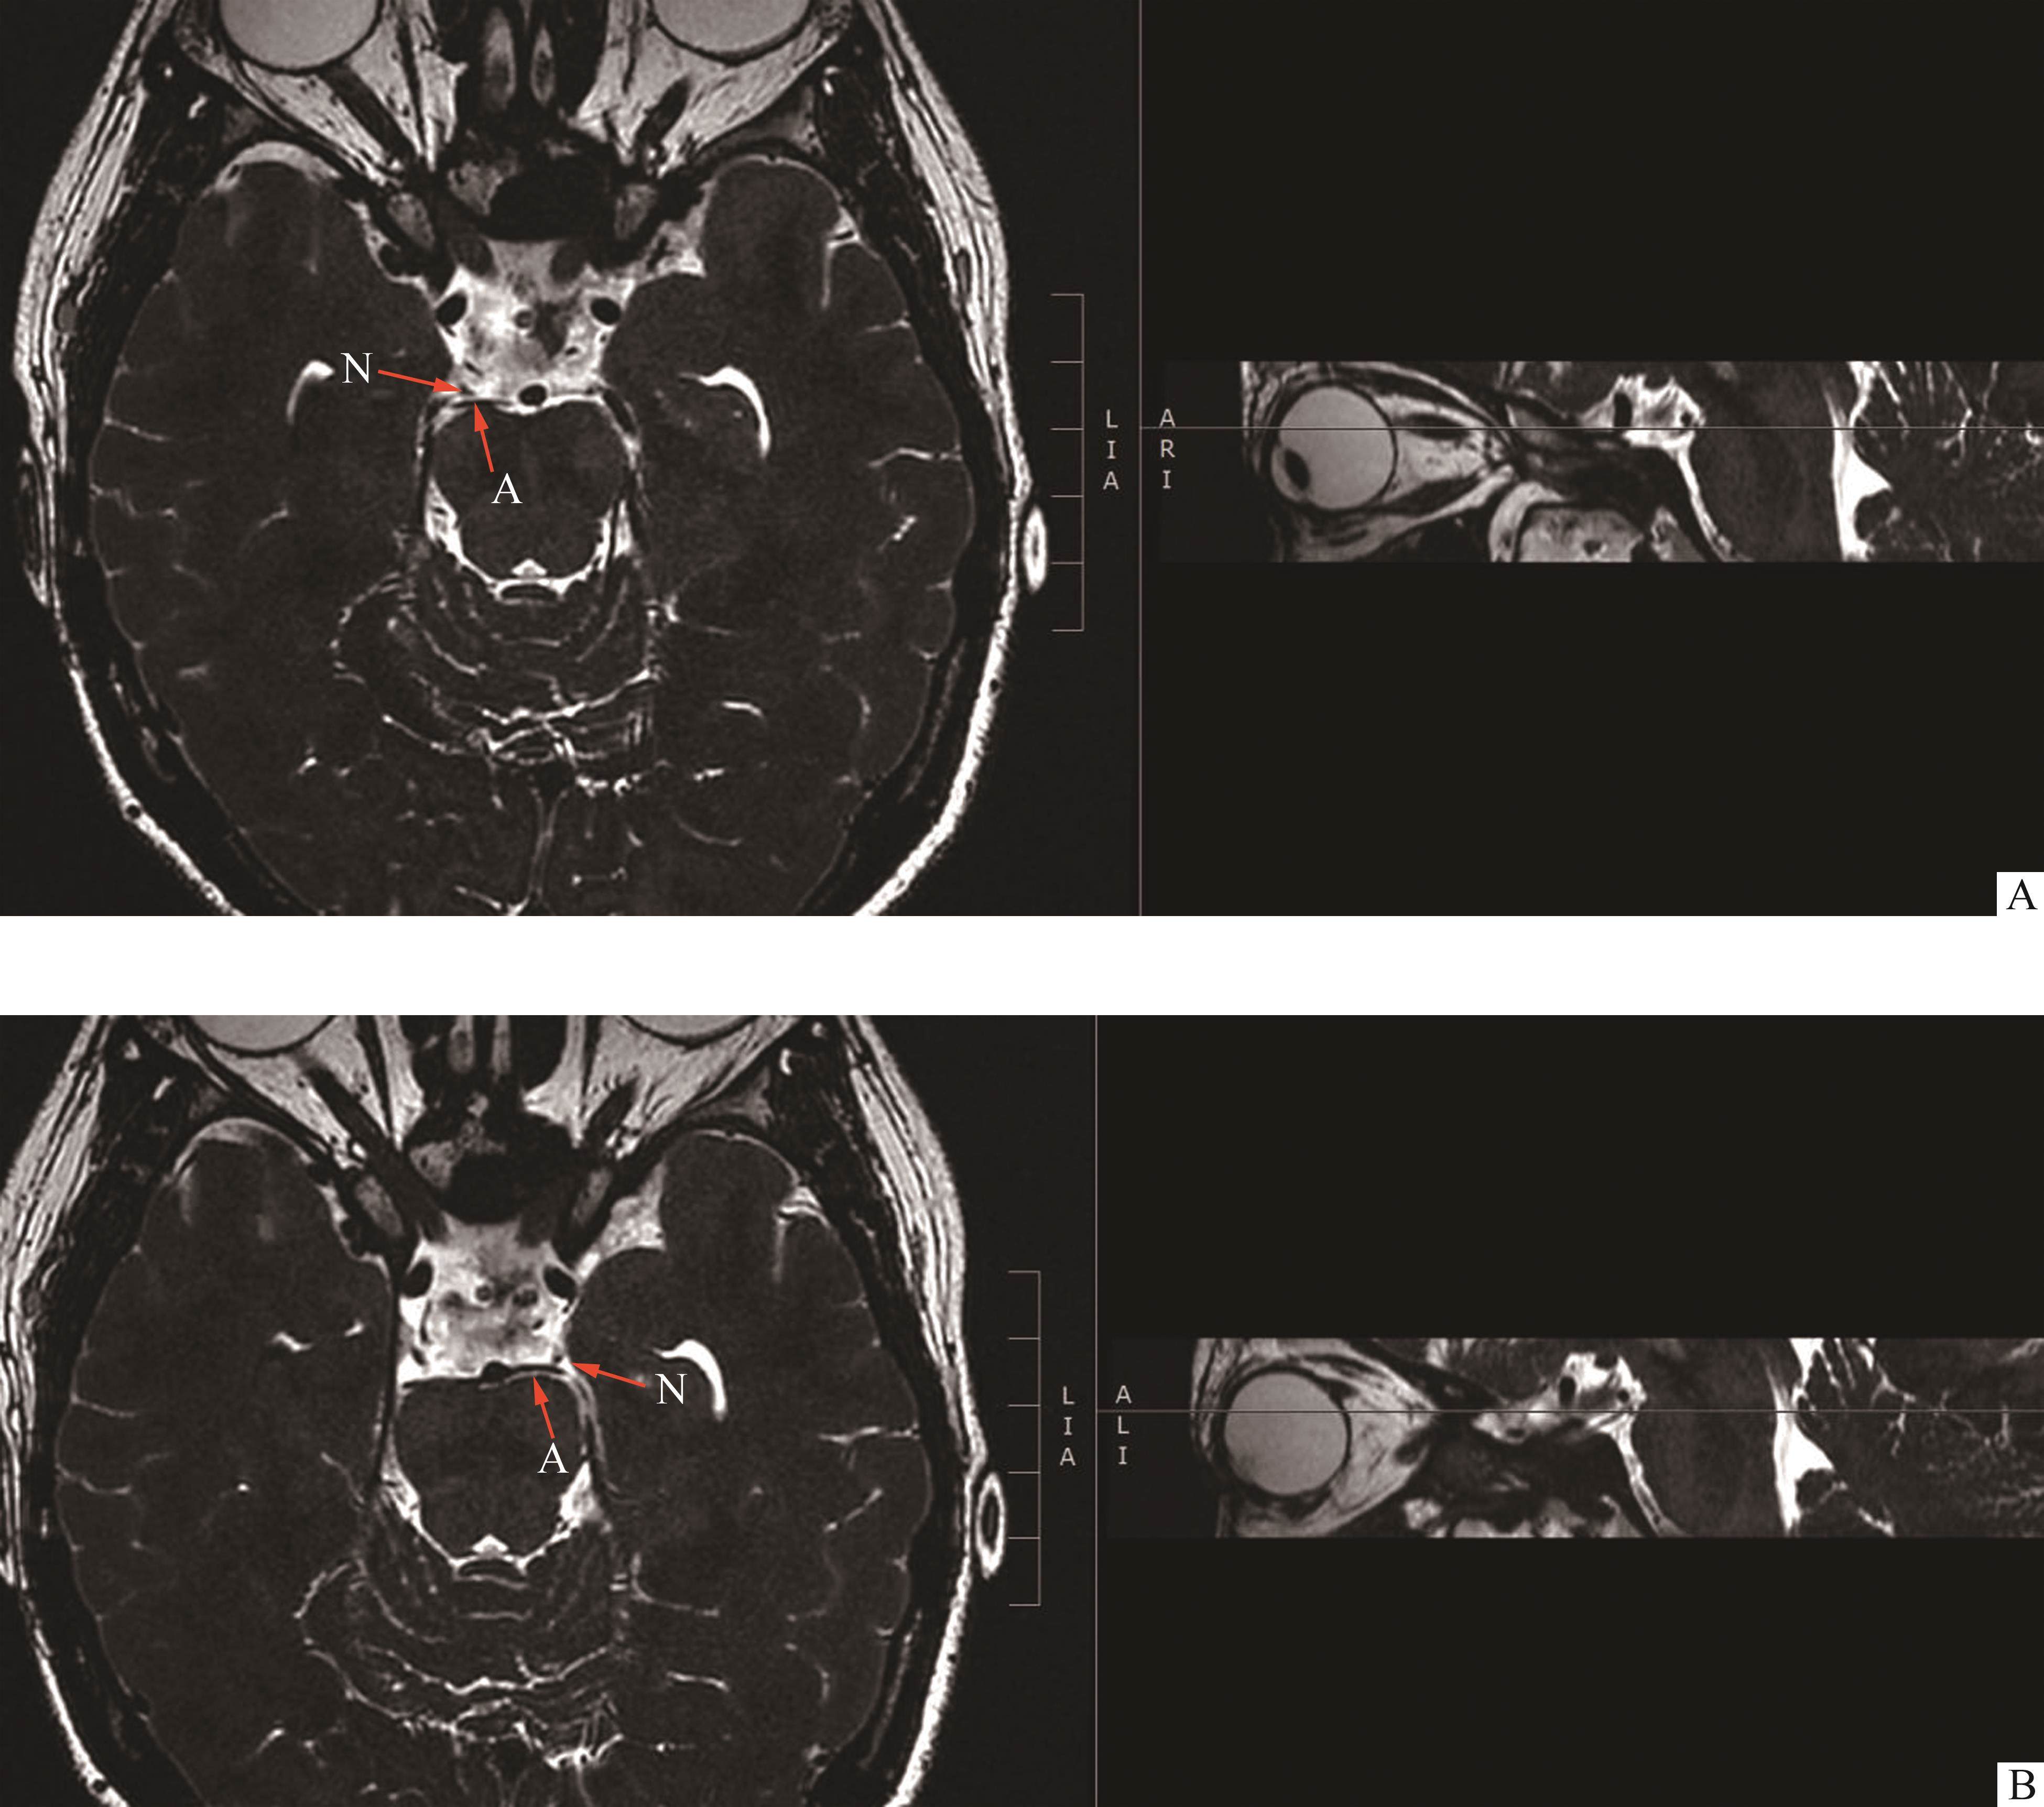

专科检查结果:1)右眼裸眼视力为0.4,左眼裸眼视力为0.8。2)外眼检查示眼睑正常,泪器、泪点正常,附属器正常。3)注视性质为中心注视。4)无代偿头位。5)双眼运动为双眼向上、向下运动减弱(图1)。6)斜视度为L/R 30△。7)右眼上睑下垂(图1C),右眼睑裂高度为4.5 mm,左眼睑裂高度为9 mm;右眼提上睑肌肌力为0,左眼提上睑肌肌力为8,双眼Bell征阴性;右眼瞳孔直径为3~4 mm,左眼瞳孔直径为2.5 mm。8)无眼球震颤。9)主导眼为右眼。10)屈光介质正常。11)眼底未见明显异常。验光结果:右眼+0.75/+1.0*100→0.8;左眼+0.5/+0.5*80→1.0。患儿动眼神经磁共振平扫+增强+水成像(图2)结果示双侧动眼神经脑池段血管接触阳性。

患儿母亲情况:母亲自小左眼眼睑下垂。双眼向上、向下运动明显减弱(图3)。斜视度为R/L 30△。有明显的左眼上睑下垂;右眼睑裂高度为12 mm,左眼睑裂高度为0.5 mm,右眼提上睑肌肌力为9 mm,左眼提上睑肌肌力为0 mm,双眼Bell征为阴性。患儿母亲动眼神经磁共振平扫+增强+水成像(图4)结果示左侧动眼神经较对侧纤细,双侧动眼神经桥前池段血管接触阳性。